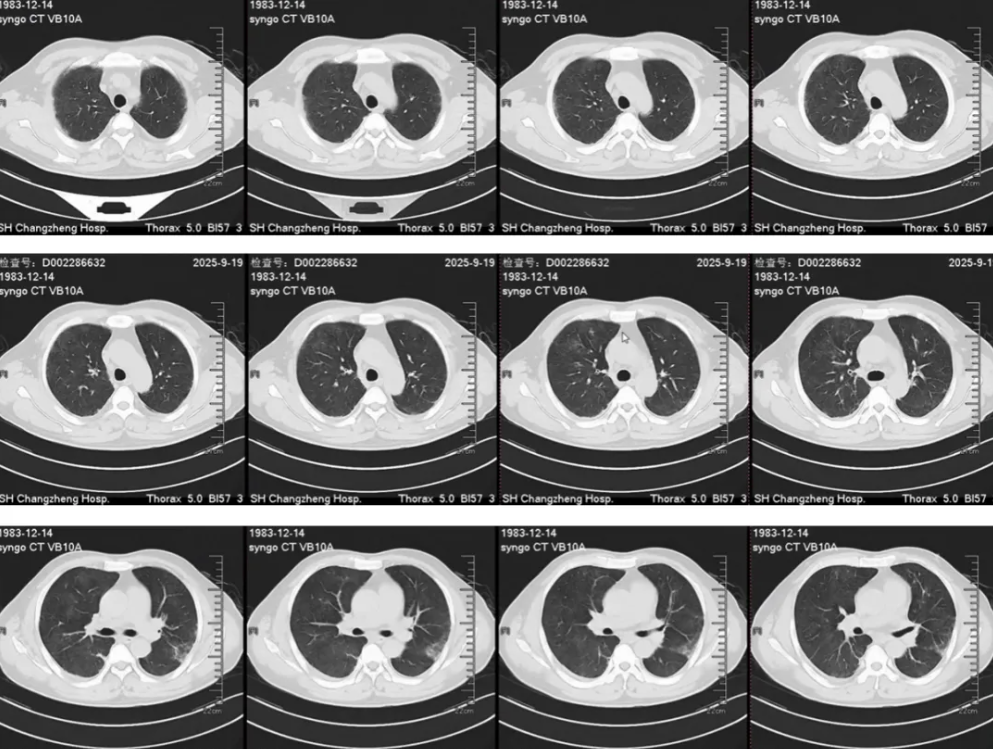

胸部CT(2025-9-18):双肺多发炎症,纵隔内及双侧腋窝见多发稍大淋巴结影,心隔角肿大淋巴结,双侧胸腔少量积液(图见后)。

胸部CT(2025-9-18)

影像表现:双肺间质和肺泡浸润影,HRCT显示边界不清的磨玻璃结节(100%)和小叶间隔增厚(90%),双侧胸腔积液(76%),气体陷闭(55%)。

影像表现:双肺、弥漫、上肺外周分布(25%)、边界不清、游走性,对激素治疗敏感,空洞少见。

胸部影像:肺部浸润影(50%-70%),边界不清、密度不均、外周或随机分布、可游走,对激素治疗敏感;小叶中心结节、支气管壁增厚、支气管扩张;小叶间隔增厚、纵膈淋巴结肿大、胸水、心包积液。 实验室检查:外周血嗜酸细胞百分比>25%,通常>40%,40%患者p-ANCA阳性,阴性不能排除诊断,抗体滴度与病情无关。